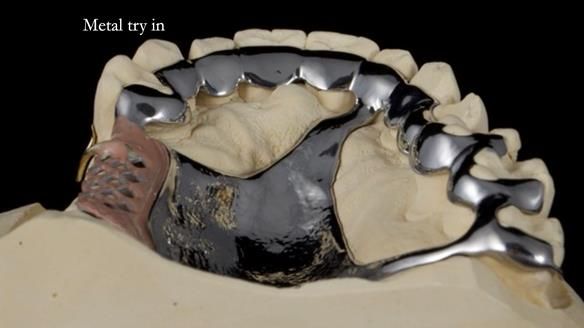

Welcome to Newsletter 64. I'll walk you through the process of providing a Mk 2 metal-based partial denture (RPD), for Ian a retired Veterinary Surgeon aged 78. The RPD was made at an increased vertical dimension and acted as an occlusal stabilisation splint - reducing the wear and bite force on the remaining natural teeth.